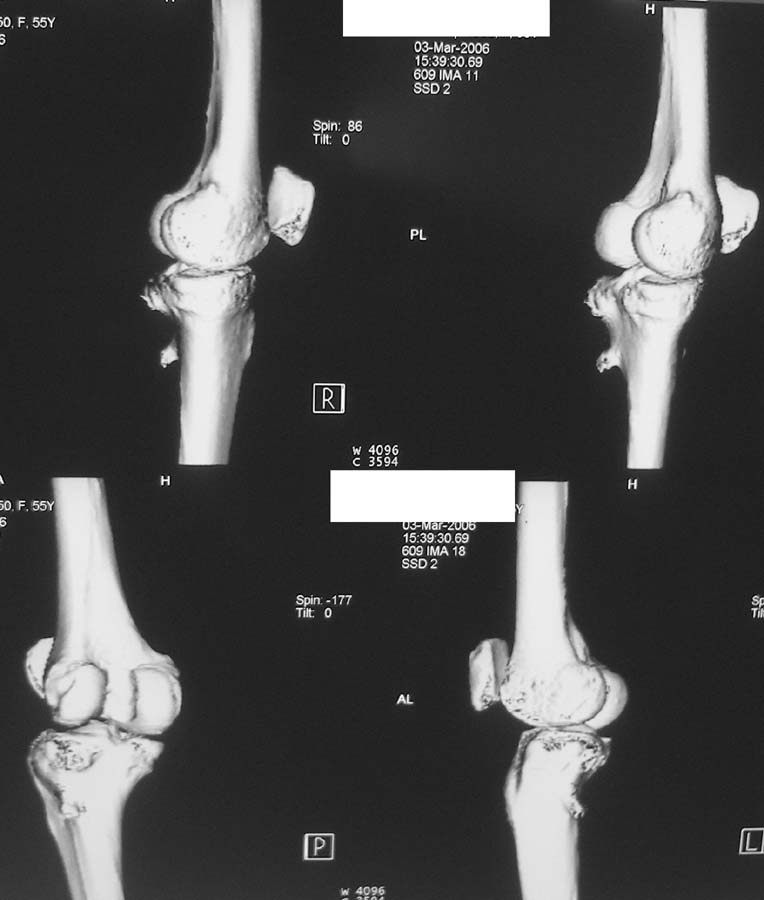

Женщина, 55 лет. С 2002 года - гонартроз. В настоящее время - боли в коленном суставе, стартовые боли, иногда в ночное время (проходит <от перемены положения ноги>).

Принимает НПВС, артрон-комплекс, внутрисуставно гиалган. Ревмопробы отрицательные. На рентгенограмме отметили сужение шейки малоберцовой кости, на спиральной КТ - экзостоз? Ваше мнение о целесообразности операции (велика вероятность повреждения нервов), предварительной биопсии?Спасибо! С уважением, А.В.Владзимирский Донецкий НИИ травматологии и ортопедии Донецк, Украина

Если боли связаны с гонартрозом, то показано тотальное эндопротезирование коленного сустава. Тип эндопротеза - мыщелковый, с сохранением задней крестовидной связки, сейчас таких моделей много (LCS, Balansis, Genesis, Scorpio, КЭКС-01 и другие, всё зависит с какими фирмами Вы работаете). Вопрос об удалении остеохондромы спорный, с одной стороны маловероятно ожидать у женщины 55 лет быстрого перерождения во вторичную хондросаркому при такой рентгенологической картине. Можно спротезировать коленный сустав и проводить рентгенконтроль каждые 6-12 мес. С другой стороны, если спротезировать и оставить остеохондрому, а она начнёт интенсивно рости, то её последующее радикальное удаление может ослабить тибиальный компонент эндопротеза. Проявляя онкологическую настороженность, остеохондрому лучше удалить первым этапом, до эндопротезирования с интервалом между операциями 6 мес. Производить биопсию в данном случае однозначно не целесообразно, так как при перерождении остеохондромы во вторичную хондросаркому на начальных стадиях малигнизации трудно гистологически отличить "добро" от "зла", и в этих ситуациях приоритет отдаётся рентгенологическим признакам. Техника операций при подобной остеохондроме стандартная - краевая резекция. Опасность повреждения малоберцового нерва существует всегда, но она зависит от мастерства хирурга и наличия микрохирургической техники (микроскоп не обязателен :)).

Вокруг коленного сустава беcсимптомные экзостозы встречаются очень часто, но они больше с медиальной стороны бедра и большеберцовой кости, и они выявляются при случайных рентгенологических исследованиях. Если нет сиптомов давления на малоберцовой нерв, то нет смысла из трогать, удаляется тогда, когда идет рост, поэтому только

наблюдение.

Насчет протезирования коленного сустава - при таком сохранном суставе навряд ли можно согласиться и совершенно согласен с Яковом, что надо искать источника боли сканированием или магнеторезонансными исследованиями.

Суставная щель на вид очень даже приличная. Мне кажется у больной есть варусная деформация колена, и возмможно с этим связано дегенаративное поражение медиального мениска и вся клиническая картина. Если это так, то эндопртезирование это слишком! Может что полегче: артроскопия и медиальная плюс-остеотомия.

Экзостоз скорее всего случайная находка, но динамического наблюдения безусловно требует.